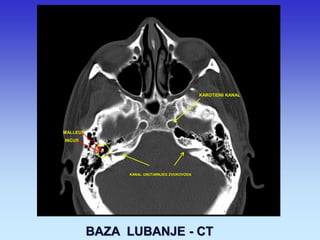

BAZA LUBANJE - CT

KAROTIDNI KANAL

SLUŠNE KOŠĆICE

MALLEUS

INCUS

KANAL UNUTARNJEG ZVUKOVODA

MALLEUS INCUS